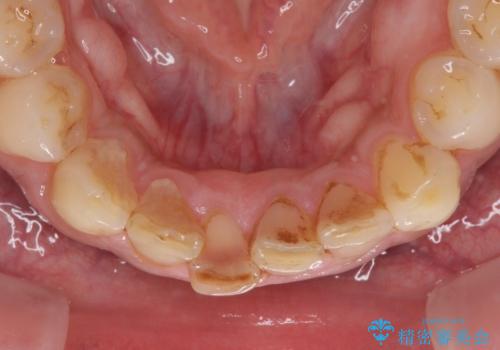

- 下の前歯がすり減って、痛みがあるとのことで来院された患者様です。

咬合力が強く、4本のうち3本の歯が失活しており、腫れや痛みが認められました。

3歯に根管治療を行い、その後4歯をオールセラミッククラウンにて補綴することとしました。